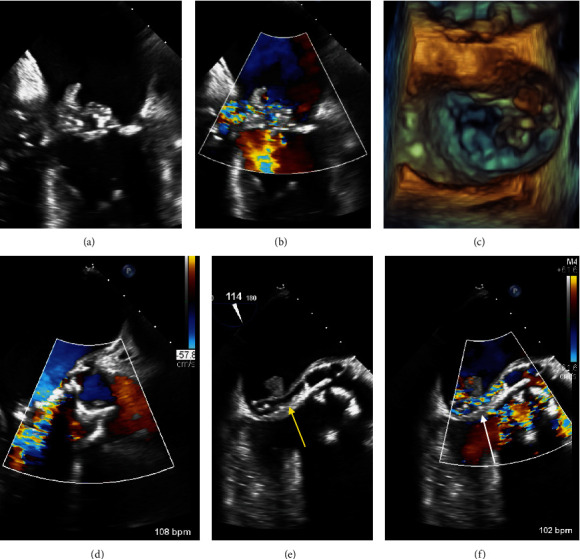

主动脉心房瘘是感染性心内膜炎的一种罕见并危及生命的并发症,通常通过观察主动脉和心房之间的连接并伴有连续血流来诊断。一名患者患有生物人工瓣膜和原生瓣膜肠球菌性心内膜炎,并伴有多种并发症,其中包括经食道超声心动图彩色 M 型诊断出的主动脉心房瘘。我们回顾了主动脉心房瘘的特征,并利用这个病例展示了如何利用 M 模式在诊断不确定的情况下提供更好的时间分辨率。

Aorto-atrial fistula is a rare and life-threatening complication of infective endocarditis, classically diagnosed by visualizing a connection between the aorta and atrium with associated continuous flow. A patient presented with bioprosthetic and native valve enterococcal endocarditis with multiple complications, including an aorto-atrial fistula that was diagnosed by color M-mode on transesophageal echocardiography. We review the features of aorto-atrial fistula and utilize this case to demonstrate how M-mode can be leveraged to provide improved temporal resolution in the setting of diagnostic uncertainty.